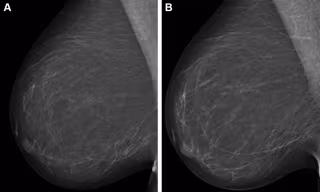

Archivo - Mamografías digitales de campo completo.

Archivo - Mamografías digitales de campo completo. - RADIOLOGICAL SOCIETY OF NORTH AMERICA - Archivo